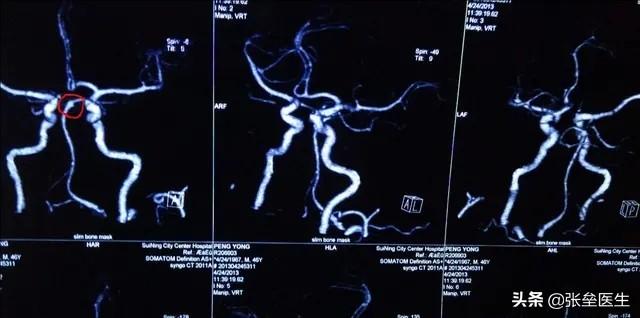

脳血管CTA

これは比較的耳にすることが少ないもので、一般的には脳動脈CTアンギオグラフィーと呼んでいます。は、より一般的な臨床CT画像診断法の一つである。造影剤を血管に注入して血管を強調させ、CTスキャン後に脳内の血管を再構成する方法は、脳内の狭窄や閉塞を特定するのに有効である。脳の血管が狭窄したり閉塞しているのは、脳の血管だけではない。多くの狭心症患者が冠動脈狭窄を考えているように、冠動脈CTAも行われるが、率直に言って、この検査の目的も血管因子が原因かどうかを確認するためである。